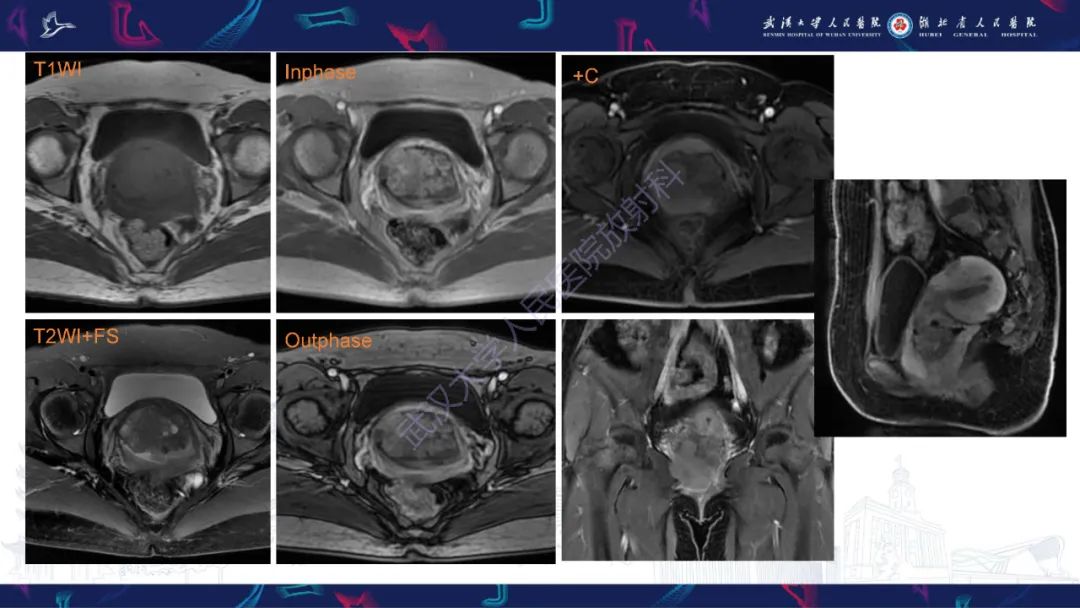

【PPT】阴道髓系肉瘤影像诊断-2